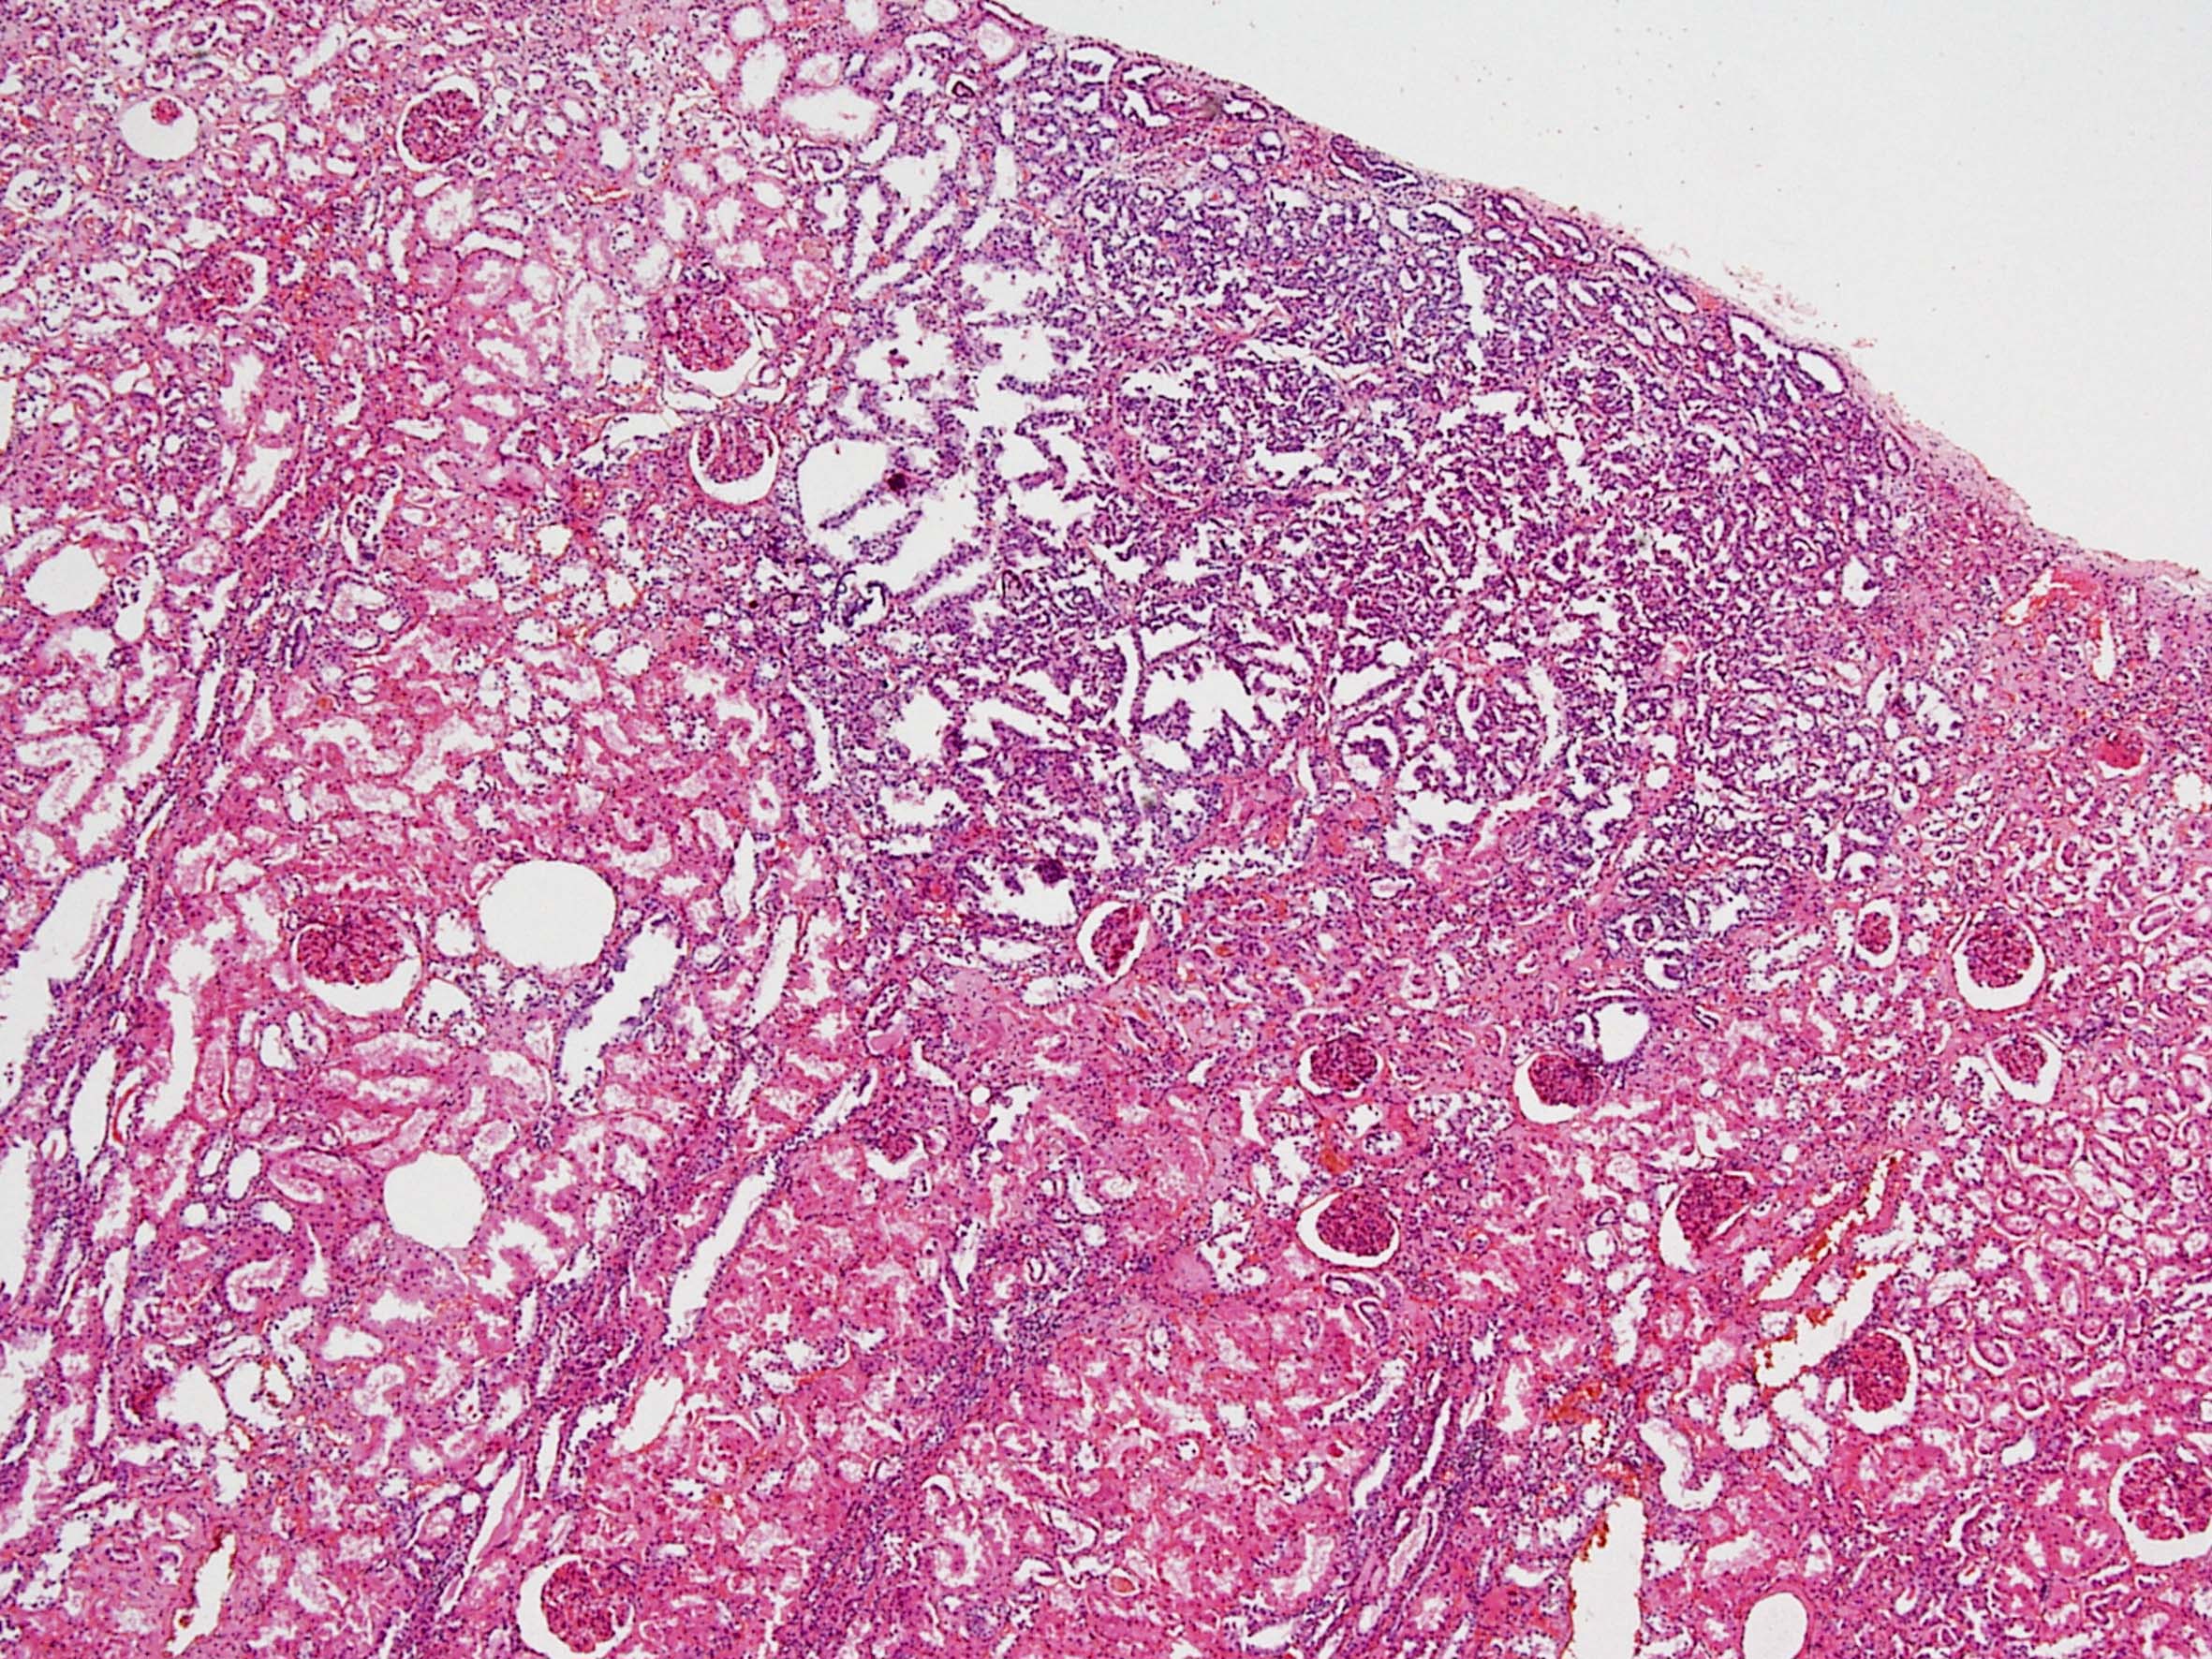

Consensus grade: I would not grade this tumor

Papillary adenoma